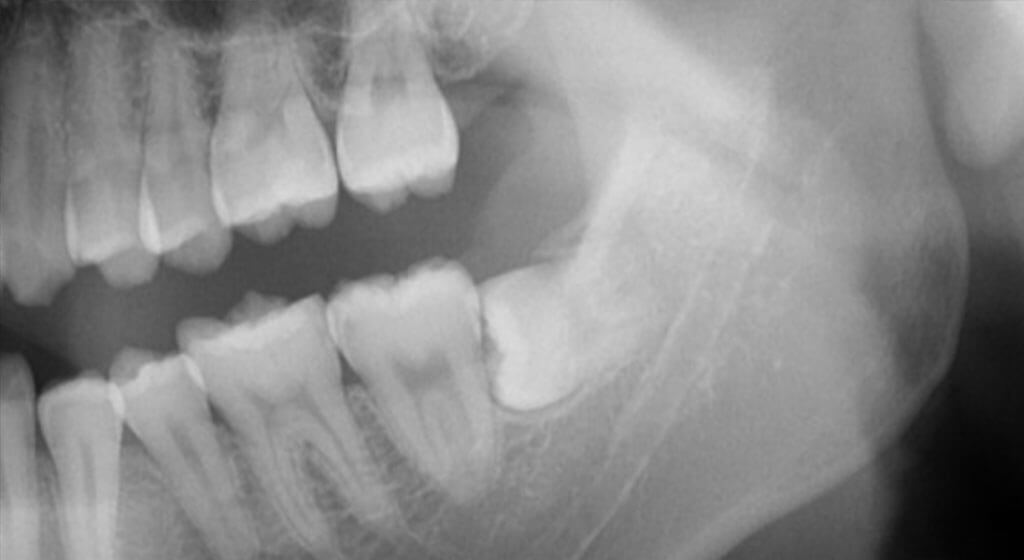

1,抜歯前のしっかりした診断

当院では下顎の神経に近い親知らずの抜歯など難しい抜歯の際には、院内のCTで撮影を行います。親知らずの根の形、下顎の神経との位置関係までを術前にきちんと把握することで、抜歯の際にかける力の方向、強さ、骨を削る部分などを予測したり、抜歯の後に起こるリスクを正確に判断することができ、より時間のかからない負担の少ない抜歯が実現できます。